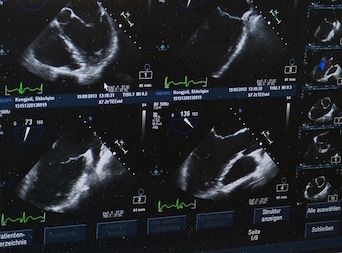

Next, CEUS was conducted using a bolus intravenous injection of contrast medium. Images were analyzed qualitatively for contrast medium distribution at designated time points: contrast uptake, peak intensity, and washout. Quantitative analysis was performed to measure several perfusion variables in pulmonary lesions, including arrival time (time when contrast enhancement reached >10% of peak intensity).

No animals experienced adverse reactions to the contrast medium. Nearly all malignant pulmonary lesions displayed inhomogeneous enhancement with variable avascularization, indicating “chaotic neoplastic neoangiogenesis and necrosis,” the researchers wrote. Most benign pulmonary lesions—particularly pneumonia—had homogeneous enhancement with linear hyperechoic structures representing typical pulmonary vessel branching.

Malignant mediastinal lesions predominantly displayed inhomogeneous enhancement. Notably, at peak intensity, homogeneity for mediastinal lymphoma varied according to lesion size: homogeneous if smaller than 50 mm and inhomogeneous if larger than 50 mm.

At peak intensity, the mediastinal abscess had homogeneous peripheral enhancement with an avascular center. Researchers indicated that this result could represent a possible advantage of CEUS over conventional ultrasonography: the ability to detect subtle differences in lesion characteristics, allowing for more accurate differentiation between malignant and benign lesions. They noted that an abscess could be misdiagnosed as a solid tumor with conventional ultrasonography.